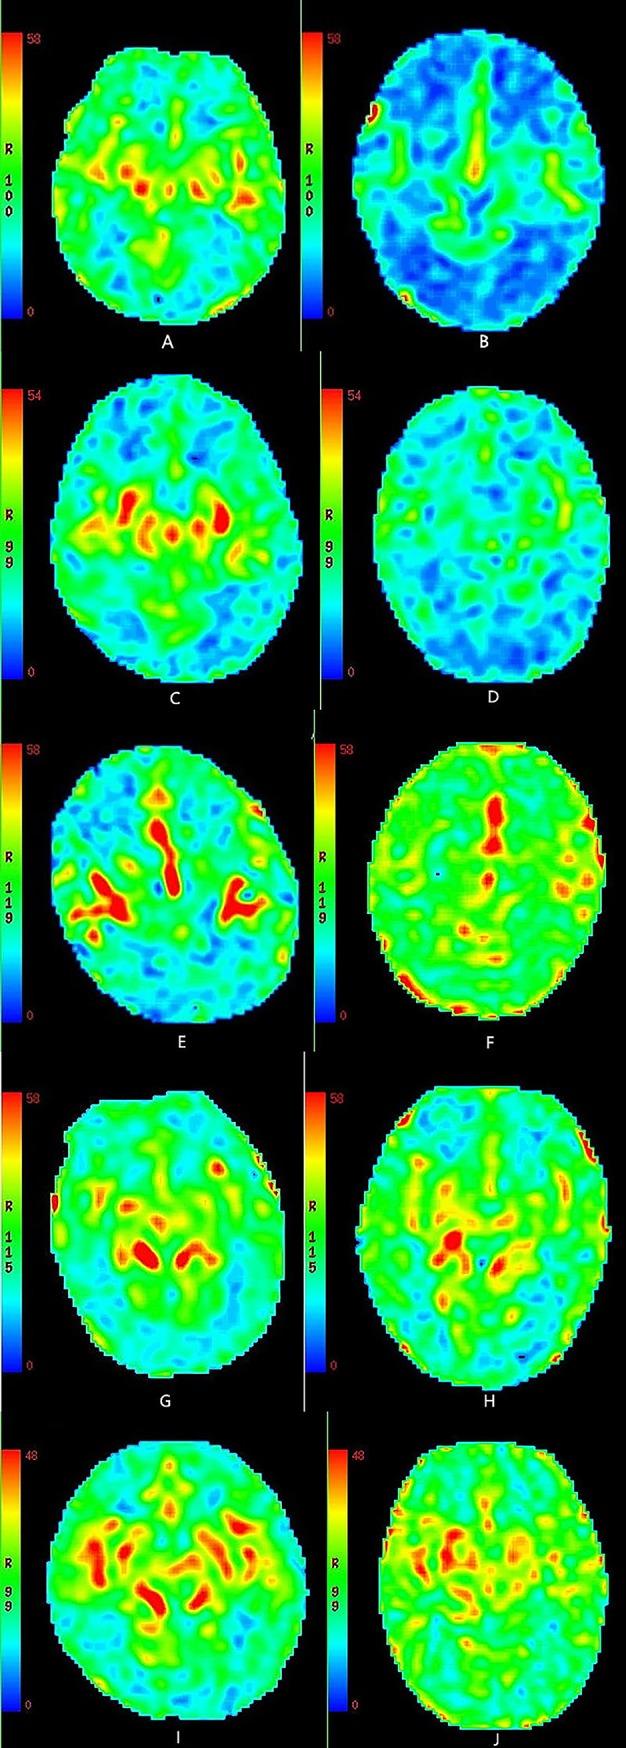

Two-hundred neonates diagnosed with neonatal HIE were equally divided into five groups (40/group): 0- to <24-hour-old HIE group, 1- to <3-day-old HIE group, 3- to <7-day-old HIE group, 7- to <15-day-old HIE group and 15- to 28-day-old HIE group; 200 healthy neonates were equivalently divided. All 10 groups received a conventional and a 3D-pcASL perfusion MRI scan. For groups <3 days old, PLD values for the 3D-pcASL cerebral perfusion MRI scan were preset at 1025 ms; in all other groups, PLD values were preset at 1525 ms. CBF values for the 3D-pcASL cerebral perfusion MRI were compared between the HIE and corresponding control groups to determine the distinguishing characteristics of CBF values in HIE neonates.

On the 3D-pcASL cerebral perfusion MRI scan, in the 1- to <3-day-old groups, HIE neonate CBF values were higher than those of controls in all brain regions (excluding the frontal lobe); in the 0- to <24-hour-old and 3- to <7-day-old groups, HIE neonate CBF values were lower than those of corresponding controls in all brain regions; in the 7- to <15-day-old and 15- to 28-day-old groups, there were no significant differences in the CBF values between groups in any brain regions.

The 3D-pcASL perfusion MRI scan combined with a PLD can assist in the early diagnosis of neonatal HIE, as this method more comprehensively reflects the HIE pathological process.